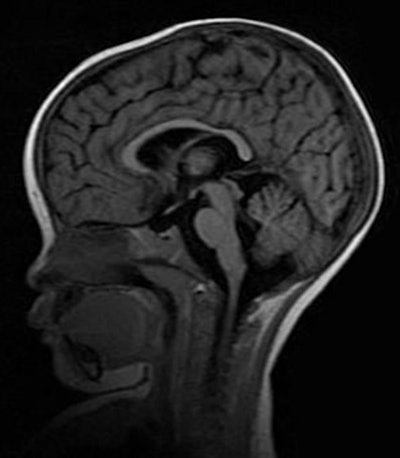

In the NEJM study, Taylor and colleagues assessed 348 children who were admitted to the hospital with cerebral malaria. Of those patients, 168 met the study criteria, including the presence of retinopathy. Twenty-five children (15%) died, and of this group, 21 (84%) had evidence of severe brain swelling on MRI when they were admitted to the hospital.

MR images revealed brain swelling in 39 (27%) of the 143 survivors, but that swelling eventually decreased after two to three days among the survivors. Taylor described that result as a "triumphant moment" in the study.

More importantly, the first piece of critical evidence came from one of the first patients scanned on the newly donated MRI. The child came to the hospital with typical cerebral malaria symptoms, including retinopathy. The comatose patient had an MRI on day 1 and a second one on day 2, but died four hours after the second scan.

While the MRI scan at autopsy revealed a swollen brain, there was no evidence of severe expansion. However, the MRI acquired during the first 24 hours after admittance showed clear evidence of the brain pushing down through a narrow hole, known as the foramen magnum, at the base of the skull.

"That area gets mushed and compressed if the brain is pushed out, and causes breathing to stop," Taylor said. "We would always look for that, but we never saw it. We could see it on the MRI and we instantly knew what happened. We never, ever would have seen it had we not captured it during life with the MRI."

Because of the pressure on the foramen magnum, the retinopathy-positive patients with cerebral malaria inevitably died because they stopped breathing.